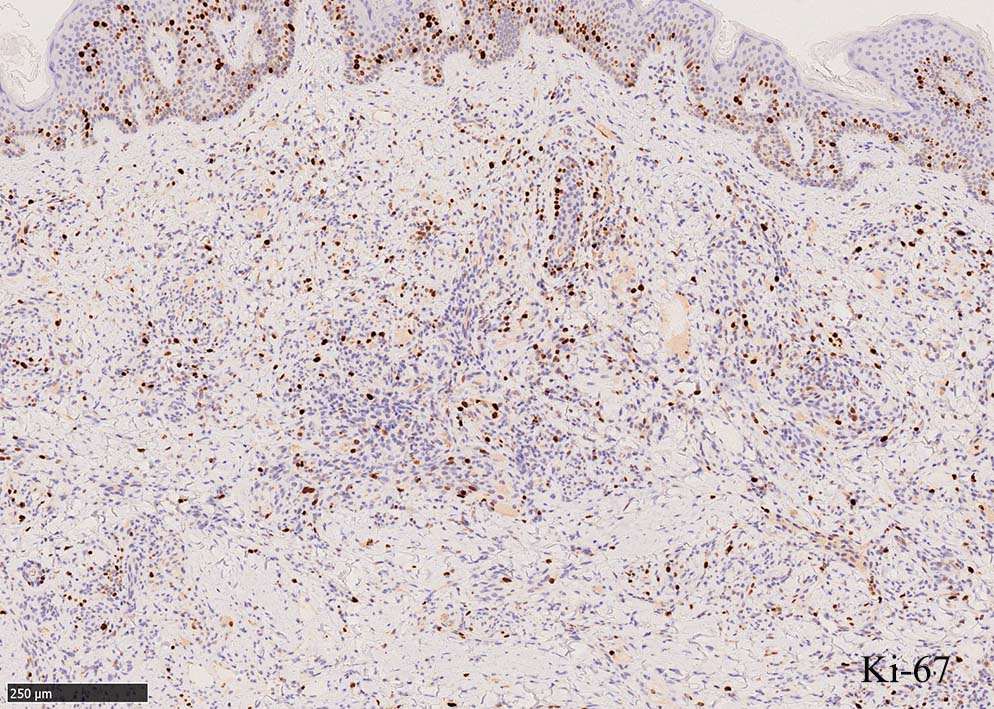

免疫染色, 分子病理学的検査

増生細胞はCD31, CD34, Factor Ⅷ, D2-40などが陽性を示す.

HHV-8の潜伏期関連抗原(HHV-8 Latency-associated nuclear antigen: HHV-8 LANA)が市販されており, 核が点状に染色される陽性所見がKaposi肉腫の確定診断に必須となっている.

細血管周囲に血管内皮様の紡錘形細胞が増生, 一部に赤血球をいれた裂隙の形成がある. 細胞の異型はみられず, mitosisの増多もない. hemosiderin-laden macrophageが散在する.

病変は真皮内に現局している. 初期斑状病変に相当すると考えられる. 本例では, 特徴とされる形質細胞浸潤増加はみられない.